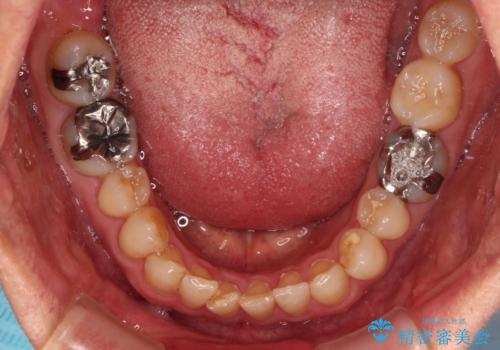

- 前歯のデコボコと隙間の空いた歯列を気にして来院された患者様です。

下顎前歯が隠れるほどのディープバイトにより、強い咬合力と突き上げで上顎歯列に隙間が空いている状態でした。

手前に傾斜している奥歯をワイヤー装置で立ち上がらせ、咬み合わせの高さを挙上することで突き上げを解消し、空隙歯列を改善していくこととしました。